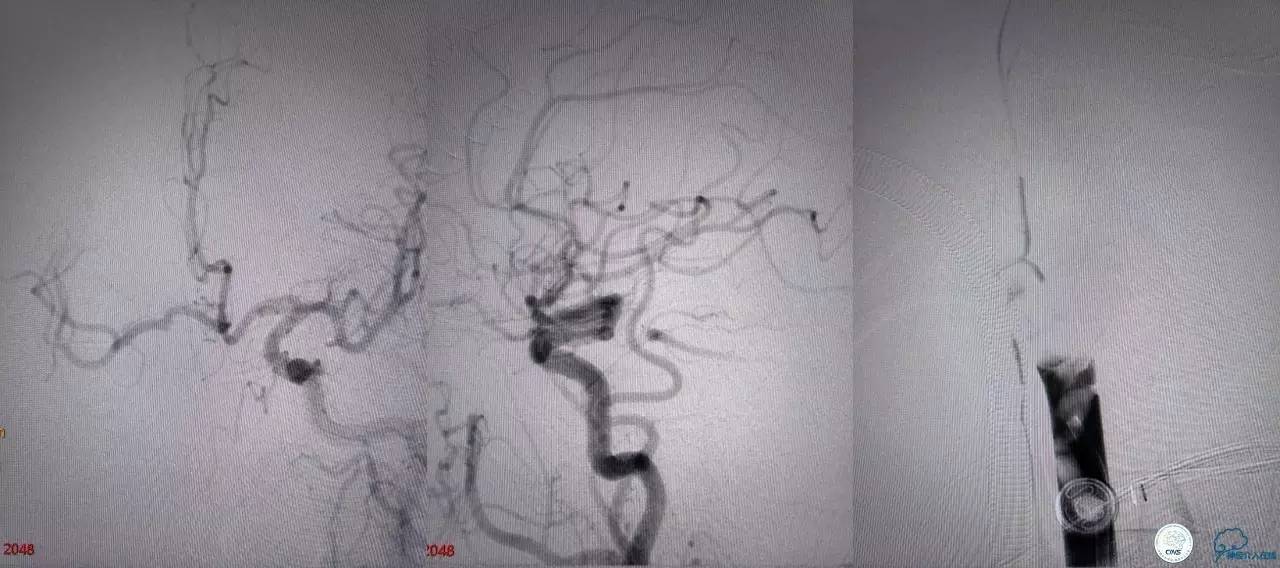

造影结果:右侧颈总动脉远端闭塞,前交通动脉开放,代偿方式:左侧颈内动脉→左侧大脑前动脉A1→前交通动脉→右侧大脑前动脉A1(反向)→右侧大脑中动脉供血区代偿。双侧大脑后动脉、右侧小脑上动脉及基底动脉顶端未见显影。

结合病史,体征及影像学,考虑患者本次发病为基底动脉尖急性闭塞,发病机制:栓塞?右侧颈总动脉慢性闭塞?非责任血管,且代偿良好,暂时不需处理!

6F导引导管到位至RV2远端,rebar-18微导管及transand微导丝至右侧大脑后动脉P1远端。

solitaireAB4-20mm支架取栓。

基底动脉顶端仍有大量血栓,双侧大脑后动脉未见显影,双侧小脑上动脉再通。再次取栓?还是动脉溶栓?